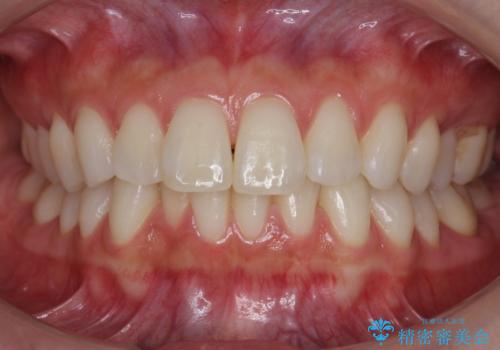

昔ワイヤー矯正をして後戻りした 軽度のがたつき モニター矯正

- 矯正治療後の後戻りを主訴に来院。

特に下の前歯のがたつきを気にされていました。

マウスピース矯正で再矯正を行いました。